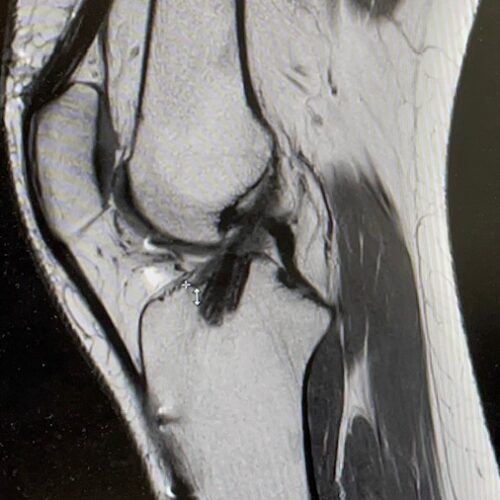

Diagnose

Het letsel van de voorste kruisband wordt bij het eerste onderzoek (bijvoorbeeld op het sportveld, spoed eisende hulp of huisarts) in het merendeel van de gevallen niet onderkend. Het stellen van de juiste diagnose is in de acute fase ook moeilijk omdat er vaak zwelling van de knie bestaat met pijn.